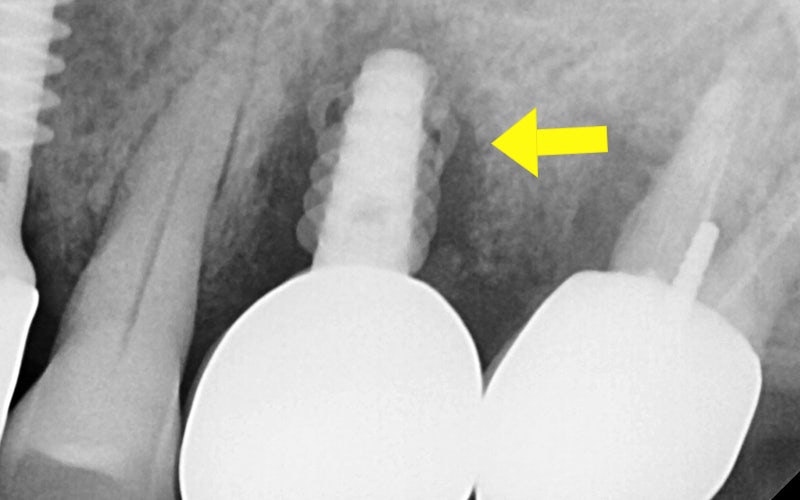

The photos above show the implant that was actually removed.

The screw body had snapped due to metal fatigue,

and around the head there was a large amount of tartar and inflammation.

The surrounding gum bone had melted away,

which eventually led to extraction of the adjacent tooth as well.